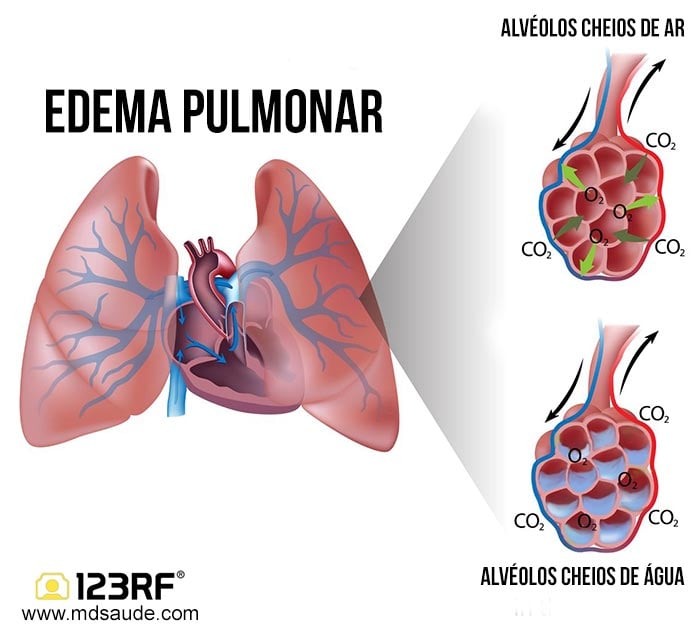

O edema pulmonar, popularmente chamado de ‘água no pulmão’, acontece quando líquido invade os alvéolos e bloqueia a entrada de oxigênio. O resultado? Uma luta desesperada por ar que pode levar à morte em minutos se não for tratada. Vamos entender o que realmente está por trás desse quadro e como reconhecer os sinais a tempo.

O edema pulmonar é o acúmulo anormal de líquido nos alvéolos, as pequenas bolsas de ar dos pulmões responsáveis pela troca de oxigênio. Quando esse líquido se acumula, a respiração se torna superficial e ineficaz, levando a uma queda rápida nos níveis de oxigênio no sangue. A causa mais comum é a insuficiência cardíaca, onde o coração não consegue bombear o sangue adequadamente, aumentando a pressão nas veias pulmonares e forçando o líquido para dentro dos alvéolos.

O edema pulmonar é, em essência, um desequilíbrio hídrico dentro do pulmão. Os alvéolos, pequenas bolsas de ar responsáveis pela troca de oxigênio e gás carbônico, ficam inundados por fluido. Isso cria uma barreira física que dificulta a passagem do oxigênio para a corrente sanguínea e a eliminação do CO2.